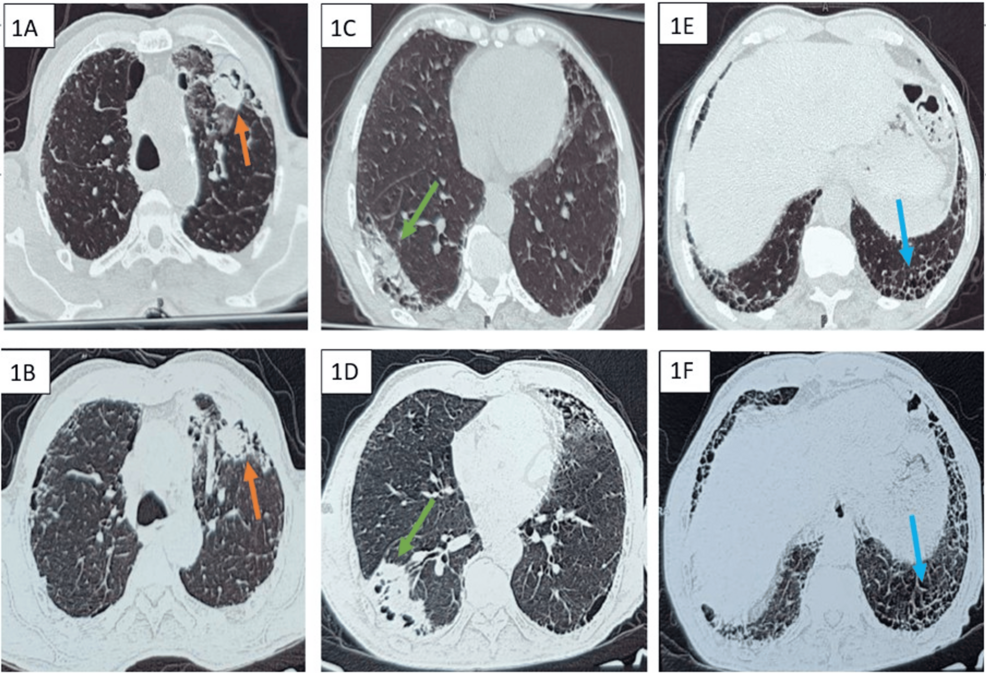

A particularly challenging case involving a patient with a history of smoking has highlighted the dangers of overlapping respiratory illnesses. Doctors recently reported a rare concurrence of idiopathic pulmonary fibrosis, chronic pulmonary aspergillosis, and lung adenocarcinoma—a combination that significantly complicates diagnosis and treatment. The case underscores the need for extensive evaluation of patients presenting with respiratory symptoms,especially those with a smoking background.

The convergence of these three conditions in a single patient is exceptionally rare. The presence of IPF can mimic some symptoms of CPA and lung cancer,potentially delaying accurate diagnosis. Similarly, the inflammation associated with CPA can obscure the early signs of adenocarcinoma. This diagnostic challenge is further compounded by the fact that smoking is a risk factor for all three diseases.

Diagnosis & Management: High-resolution computed tomography (HRCT) scans are vital for diagnosis. Treatment focuses on slowing disease progression with medications like pirfenidone and nintedanib, and pulmonary rehabilitation to improve quality of life. Lung transplantation is an option in severe cases.

Diagnosis & Treatment: diagnosis involves imaging (CT scans), sputum cultures, and sometimes bronchoscopy. treatment for CPA typically involves long-term antifungal medication.

Advances in Treatment: Early detection through low-dose CT scans is crucial. Treatment options include surgery, chemotherapy, radiation therapy, targeted therapy, and immunotherapy. The rise of precision medicine, utilizing genetic testing of the tumor, is revolutionizing adenocarcinoma treatment.